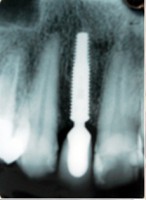

- Extração imediata

- Implante imediato

- Carga imediata